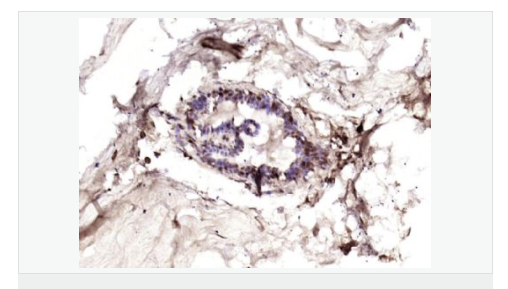

| 產(chǎn)品應(yīng)用 | ELISA=1:5000-10000 IHC-P=1:100-500 IHC-F=1:100-500 IF=1:100-500 (石蠟切片需做抗原修復(fù)) not yet tested in other applications. optimal dilutions/concentrations should be determined by the end user. |

| 產(chǎn)品介紹 | This gene is a member of the Tyr protein kinase family and the epidermal growth factor receptor subfamily. It encodes a single-pass type I membrane protein with multiple cysteine rich domains, a transmembrane domain, a tyrosine kinase domain, a phosphotidylinositol-3 kinase binding site and a PDZ domain binding motif. The protein binds to and is activated by neuregulins and other factors and induces a variety of cellular responses including mitogenesis and differentiation. Multiple proteolytic events allow for the release of a cytoplasmic fragment and an extracellular fragment. Mutations in this gene have been associated with cancer. Alternatively spliced variants which encode different protein isoforms have been described; however, not all variants have been fully characterized. [provided by RefSeq, Jul 2008]. Function: Tyrosine-protein kinase that plays an essential role as cell surface receptor for neuregulins and EGF family members and regulates development of the heart, the central nervous system and the mammary gland, gene transcription, cell proliferation, differentiation, migration and apoptosis. Required for normal cardiac muscle differentiation during embryonic development, and for postnatal cardiomyocyte proliferation. Required for normal development of the embryonic central nervous system, especially for normal neural crest cell migration and normal axon guidance. Required for mammary gland differentiation, induction of milk proteins and lactation. Acts as cell-surface receptor for the neuregulins NRG1, NRG2, NRG3 and NRG4 and the EGF family members BTC, EREG and HBEGF. Ligand binding triggers receptor dimerization and autophosphorylation at specific tyrosine residues that then serve as binding sites for scaffold proteins and effectors. Ligand specificity and signaling is modulated by alternative splicing, proteolytic processing, and by the formation of heterodimers with other ERBB family members, thereby creating multiple combinations of intracellular phosphotyrosines that trigger ligand- and context-specific cellular responses. Mediates phosphorylation of SHC1 and activation of the MAP kinases MAPK1/ERK2 and MAPK3/ERK1. Isoform JM-A CYT-1 and isoform JM-B CYT-1 phosphorylate PIK3R1, leading to the activation of phosphatidylinositol 3-kinase and AKT1 and protect cells against apoptosis. Isoform JM-A CYT-1 and isoform JM-B CYT-1 mediate reorganization of the actin cytoskeleton and promote cell migration in response to NRG1. Isoform JM-A CYT-2 and isoform JM-B CYT-2 lack the phosphotyrosine that mediates interaction with PIK3R1, and hence do not phosphorylate PIK3R1, do not protect cells against apoptosis, and do not promote reorganization of the actin cytoskeleton and cell migration. Proteolytic processing of isoform JM-A CYT-1 and isoform JM-A CYT-2 gives rise to the corresponding soluble intracellular domains (4ICD) that translocate to the nucleus, promote nuclear import of STAT5A, activation of STAT5A, mammary epithelium differentiation, cell proliferation and activation of gene expression. The ERBB4 soluble intracellular domains (4ICD) colocalize with STAT5A at the CSN2 promoter to regulate transcription of milk proteins during lactaction. The ERBB4 soluble intracellular domains can also translocate to mitochondria and promote apoptosis. Subunit: Monomer in the absence of bound ligand. Homodimer or heterodimer with another ERBB family member upon ligand binding, thus forming heterotetramers. Interacts with EGFR and ERBB2. Interacts with CBFA2T3 (By similarity). Interacts with DLG2 (via its PDZ domain), DLG3 (via its PDZ domain), DLG4 (via its PDZ domain) and SNTB2 (via its PDZ domain). Interacts with MUC1. Interacts (via its PPxy motifs) with WWOX. Interacts (via the PPxY motif 3 of isoform JM-A CYT-2) with YAP1 (via the WW domain 1 of isoform 1). Interacts (isoform JM-A CYT-1 and isoform JM-B CYT-1) with WWP1. Interacts (via its intracellular domain) with TRIM28. Interacts (via the intracellular domains of both CYT-1 and CYT-2 isoforms) with KAP1; the interaction does not phosphorylate KAP1 but represses ERBB4-mediated transcriptional activity. Interacts with PRPU, DDX23, MATR3, RBM15, ILF3, KAP1, U5S1, U2SURP, ITCH, HNRPU, AP2A1, NULC, LEO1, WWP2, IGHG1, HXK1, GRB7 AND ARS2. Interacts (phosphorylated isoform JM-A CYT-1 and isoform JM-B CYT-1) with PIK3R1. Interacts with SHC1. Interacts with GRB2. Interacts (soluble intracellular domain) with STAT5A. Interacts (soluble intracellular domain) with BCL2. Interacts (phosphorylated) with STAT1. Subcellular Location: Cell membrane; Single-pass type I membrane protein. Note=In response to NRG1 treatment, the activated receptor is internalized. ERBB4 intracellular domain: Nucleus. Mitochondrion. Note=Following proteolytical processing E4ICD (E4ICD1 or E4ICD2 generated from the respective isoforms) is translocated to the nucleus. Significantly more E4ICD2 than E4ICD1 is found in the nucleus. E4ICD2 colocalizes with YAP1 in the nucleus. Tissue Specificity: Expressed at highest levels in brain, heart, kidney, in addition to skeletal muscle, parathyroid, cerebellum, pituitary, spleen, testis and breast. Lower levels in thymus, lung, salivary gland, and pancreas. Isoform JM-A CYT-1 and isoform JM-B CYT-1 are expressed in cerebellum, but only the isoform JM-B is expressed in the heart. Post-translational modifications: Isoform JM-A CYT-1 and isoform JM-A CYT-2 are processed by ADAM17. Proteolytic processing in response to ligand or 12-O-tetradecanoylphorbol-13-acetate stimulation results in the production of 120 kDa soluble receptor forms and intermediate membrane-anchored 80 kDa fragments (m80HER4), which are further processed by a presenilin-dependent gamma-secretase to release a cytoplasmic intracellular domain (E4ICD; E4ICD1/s80Cyt1 or E4ICD2/s80Cyt2, depending on the isoform). Membrane-anchored 80 kDa fragments of the processed isoform JM-A CYT-1 are more readily degraded by the proteasome than fragments of isoform JM-A CYT-2, suggesting a prevalence of E4ICD2 over E4ICD1. Isoform JM-B CYT-1 and isoform JM-B CYT-2 lack the ADAM17 cleavage site and are not processed by ADAM17, precluding further processing by gamma-secretase. Autophosphorylated on tyrosine residues in response to ligand binding. Autophosphorylation occurs in trans, i.e. one subunit of the dimeric receptor phosphorylates tyrosine residues on the other subunit. Ligands trigger phosphorylation at specific tyrosine residues, thereby creating binding sites for scaffold proteins and effectors. Constitutively phosphorylated at a basal level when overexpressed in heterologous systems; ligand binding leads to increased phosphorylation. Phosphorylation at Tyr-1035 is important for interaction with STAT1. Phosphorylation at Tyr-1056 is important for interaction with PIK3R1. Phosphorylation at Tyr-1242 is important for interaction with SHC1. Phosphorylation at Tyr-1188 may also contribute to the interaction with SHC1. Isoform JM-A CYT-2 is constitutively phosphorylated on tyrosine residues in a ligand-independent manner. E4ICD2 but not E4ICD1 is phosphorylated on tyrosine residues. Ubiquitinated. During mitosis, the ERBB4 intracellular domain is ubiquitinated by the APC/C complex and targeted to proteasomal degradation. Isoform JM-A CYT-1 and isoform JM-B CYT-1 are ubiquitinated by WWP1. The ERBB4 intracellular domain (E4ICD1) is ubiquitinated, and this involves NEDD4. Similarity: Belongs to the protein kinase superfamily. Tyr protein kinase family. EGF receptor subfamily. Contains 1 protein kinase domain. SWISS: Q15303 Gene ID: 2066 Database links: Entrez Gene: 2066 Human Entrez Gene: 13869 Mouse Omim: 600543 Human SwissProt: Q15303 Human SwissProt: Q61527 Mouse Unigene: 390729 Human Unigene: 442420 Mouse Unigene: 163078 Rat Important Note: This product as supplied is intended for research use only, not for use in human, therapeutic or diagnostic applications. 細(xì)胞膜受體(Membrane Receptors) c-erbB-4蛋白過(guò)去一直為乳腺癌基因研究的主要方向,研究乳腺癌組織學(xué)分級(jí)及術(shù)后生存期的關(guān)系。目前認(rèn)為他與細(xì)胞增殖活性和激素受體有一定的關(guān)聯(lián),有學(xué)者將c-erbB-4蛋白研究用于神經(jīng)內(nèi)分泌蛋白為主。 |